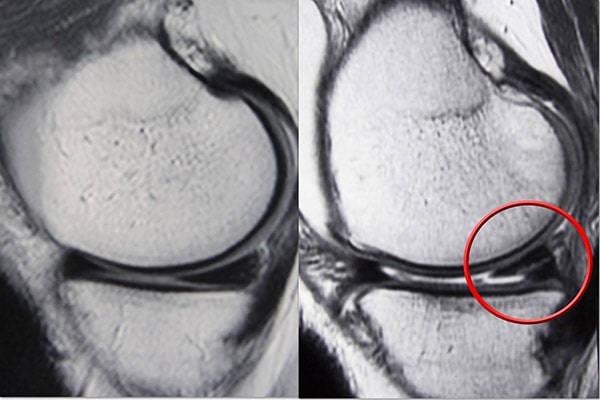

磁共振成像 (MRI) 掃描。 MRI 掃描可評估膝關節的軟組織,包括半月板、軟骨、肌腱和韌帶。

成像測試

由于其他膝蓋受傷也會引起類似的癥狀,您的醫生可能會要求進行影像學檢查以幫助確認診斷。